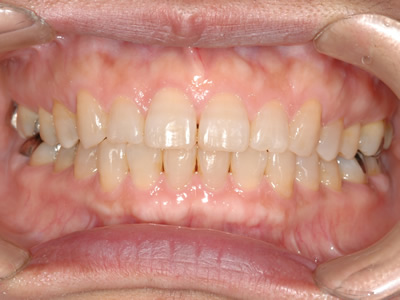

永久歯に交換するためのスペース不足による前歯のガタガタで、取り外しができる拡大床にて上下顎の幅を拡大した後、上顎の前歯をマルチブラケット装置で並べました。治療の期間は1年9か月でした。

初診時

終了時